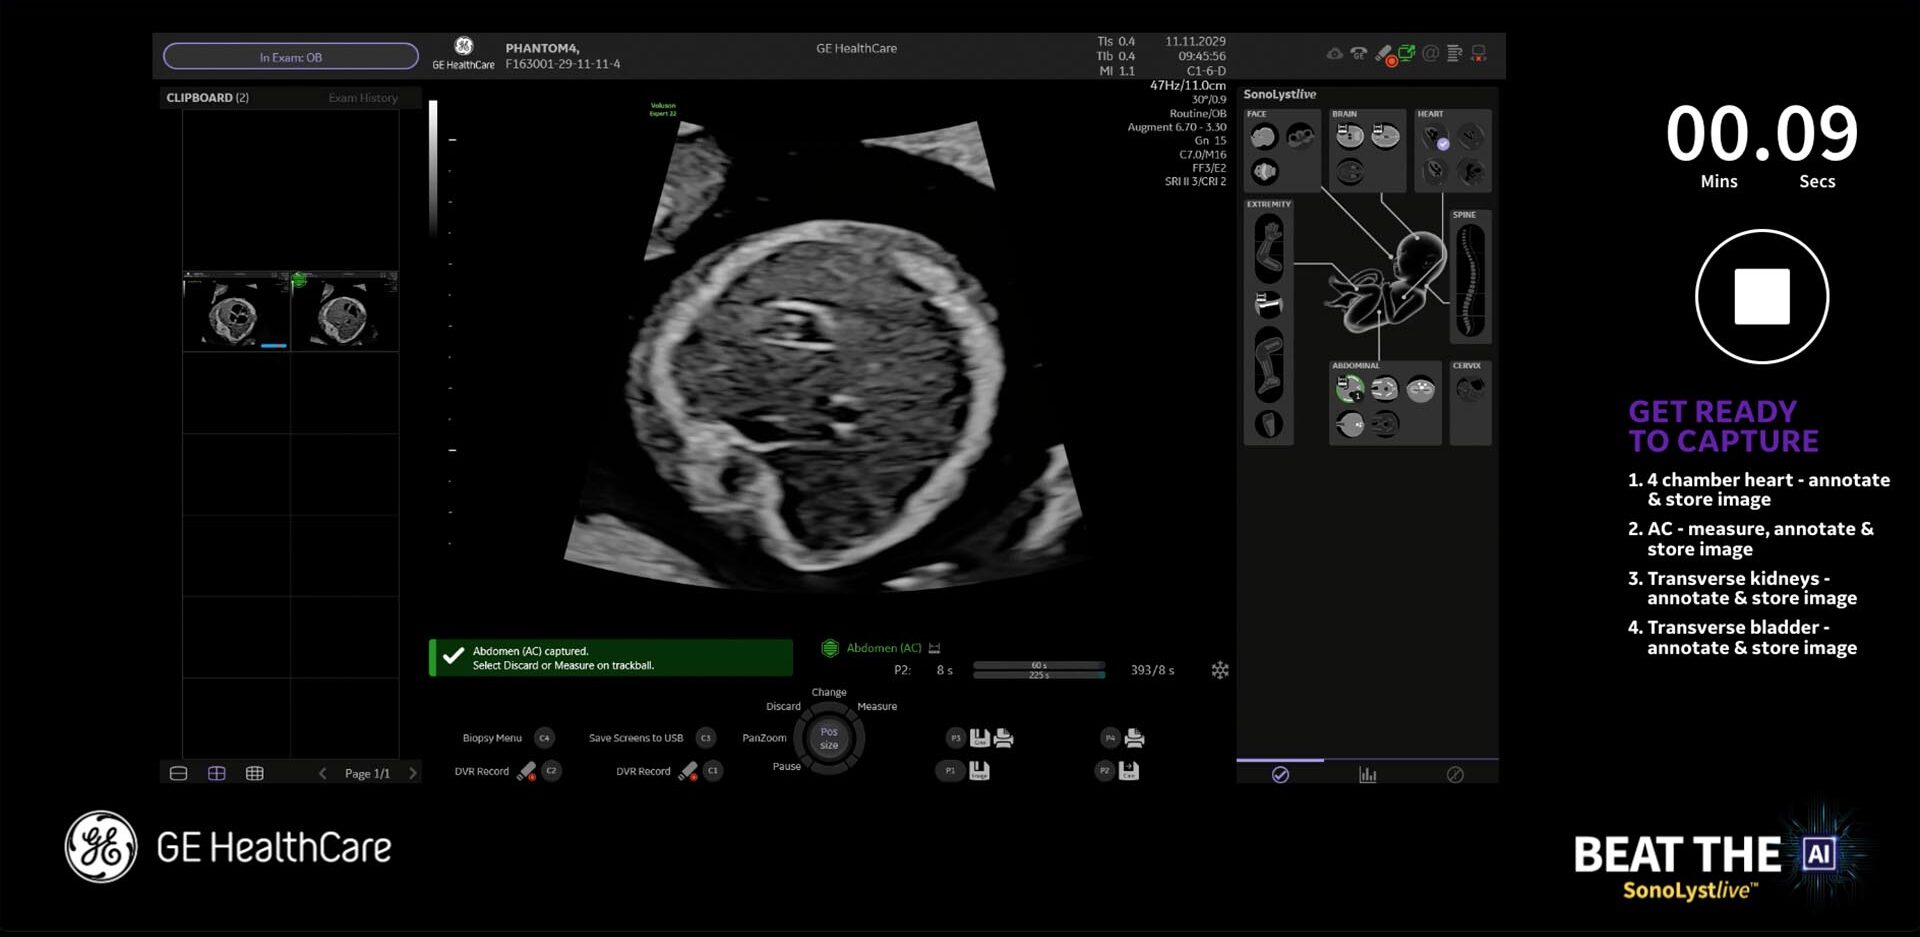

Using a combination of strategic insight and a creative ideation process, the team at TrunkBBI developed multiple game ideas, from a simple quiz to a more complex ‘Beat the AI’ concept, allowing sonographers to test their skills against a pre-programmed scan in real-time. The intent was for this to showcase the incredible power of GE HealthCare’s machine AI capability, and prove to our audience how it could help reduce scanning time in a busy role.

The concepts worked on multiple levels – continuing with GE HealthCare’s goal of highlighting new ultrasound machine updates, and as a way to engage more fully with BMUS attendees and collect information for follow-up.